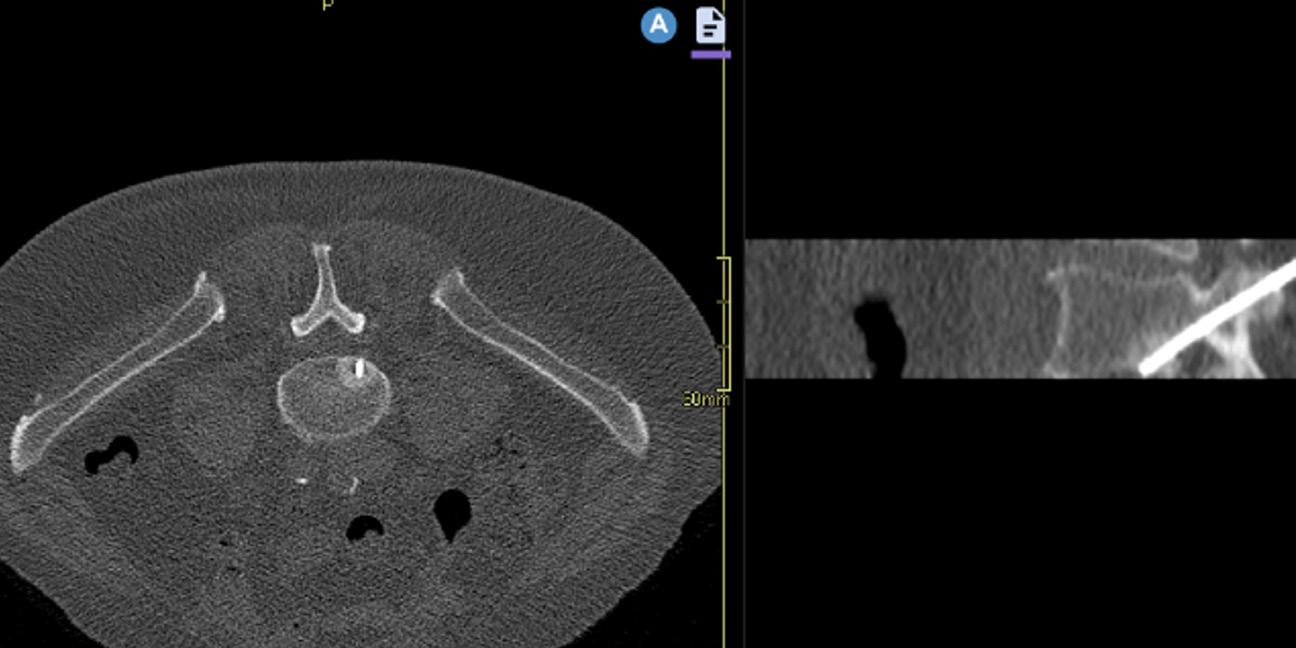

Förutsättningen för att kunna göra bilder i flera plan och 3D-rekonstruktioner kom i och med den digitala revolutionen kring millennieskiftet då RIS och PACS snabbt introducerades över landet. Bild 2. Mycket av utvecklingen leddes av det svenska företaget Sectra som idag har ungefär hälften av den svenska marknaden. Eftersom CT-detektorerna ger bilder som är 0,625 mm tunna och detektorraderna innehåller fler än 1000 detektorer blir

voxlarna i princip istotropa, vilket gör att man i PACS kan vrida och vända på bilderna i valfritt betraktningsplan med bibehållen bildkvalitet. Trenden går nu mot att användaren själv skapar de bilder som behövs från de tunna axiala snitten och färdiga rekonstruktioner av tjockare snitt i de tre ortogonala planen behövs snart inte längre. Det förenklar hanteringen för röntgensjuksköterskan som gör undersökningen, men ställer större krav på radiologer och ortopeder att känna till hur bilderna ska betraktas för att få en standardiserad bild. Utan en standardiserad normalbild där man lär sig hur frånvaron av patologi ser ut är det svårt att känna igen patologi.

Bild 1. Den första skalldatortomografen från EMI. Foto Mats Geijer i Deutsches Röntgenmuseum, Remscheid-Lennep. Bild 2. Patient med scapulafraktur. I ett modernt PACS kan patologin demonstreras i tre invinklade plan samt 3D-rekonstruktion samtidigt.

reduceras en hel del utan påverkan på bildkvaliteten eftersom skelett har en hög inneboende kontrast visavi omgivande mjukdelar. Det är fullt möjligt att göra CT till samma organdos som för röntgenundersökning, till exempel ländrygg2 vilket ger en CT av förhållandevis låg kvalitet med hög brusnivå, men som ändå ger mera diagnostisk information än motsvarande röntgenundersökning tack vare den tomografiska metoden och tredimensionell datavolym. Det kan dock krävas en del justeringar av inställningar för att få en så bra lågdosundersökning som möjligt. Bild 3.

Bild 3. Lågdos-CT av en äldre patient med långdragen ankyloserande spondylit med ankylos i kotpelare och sacroiliacaleder. Sagittal reformatering och 3D-rekonstruktion. Bild 4. Cone-beam-CT med stol för patienten och vinklat gantry. Foto Mats Geijer.